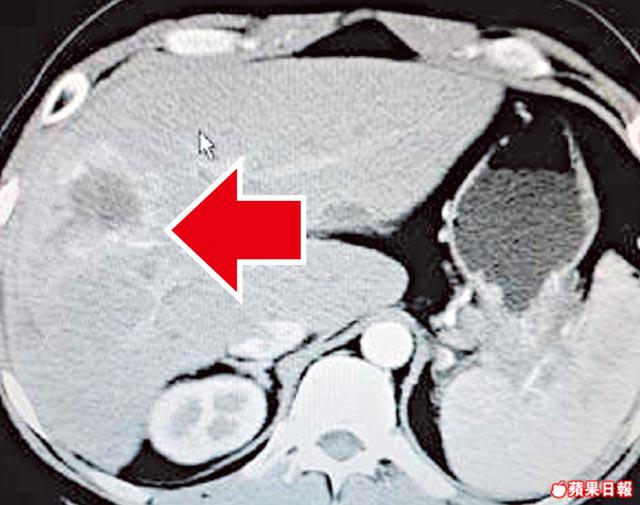

瑪麗醫院內科腫瘤科醫生梁澄宇表示,NET成因不明,可潛伏三至六年才有病徵。但年初有一名21歲少女確診,她持續肚痛兩至三個月,經電腦掃描後發現肝臟有兩個擴散性腫瘤,手術切除後發現是NET,「但未搵到原位神經內分泌腫瘤」,現正接受觀察,暫未知是否出現擴散。

梁續稱,如發現上述病徵,可透過電腦掃描、體抑素受體閃爍攝影、正子電腦斷層掃描等,檢查是否患有NET,找出其位置及觀察是否已擴散;並可透過手術或藥物進行治療。